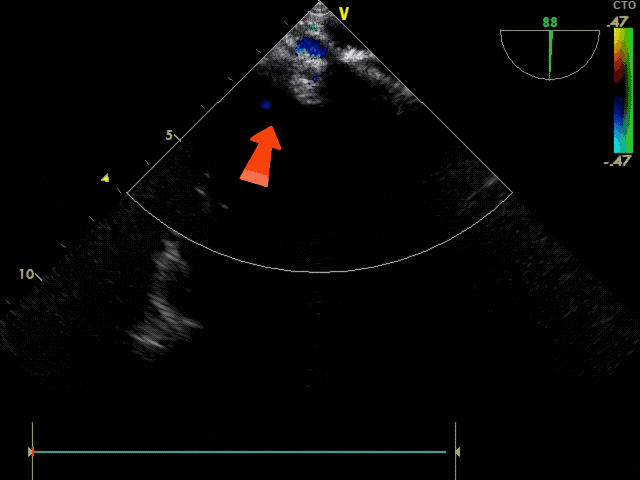

锁定前观察

锁定前观察,确认封堵器骑跨于房间隔两侧,稳固夹持

彩色血流观察